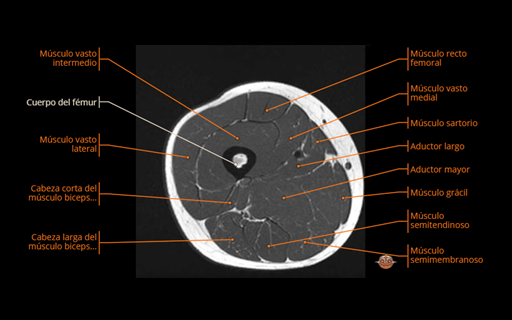

El fémur es el hueso largo más grande del cuerpo y se divide en epífisis proximal (cabeza femoral que articula con el acetábulo, cuello, trocánter mayor y menor), diáfisis (con la línea áspera en su cara posterior) y epífisis distal (cóndilos medial y lateral, escotadura intercondílea y superficie patelar). Sirve de anclaje a numerosos músculos: en la porción proximal se insertan glúteo medio y menor (trocánter mayor), iliopsoas (trocánter menor) y cuadrado femoral/rotadores cortos (cresta intertrocantérica); en la diáfisis, la línea áspera recibe a los aductores (largo, corto y mayor), parte del bíceps femoral (cabeza corta) y origina fibras de vasto medial y lateral; en la distal, alrededor de los cóndilos, se originan gastrocnemio lateral y medial y se insertan plantar y poplíteo; anteriormente, el vasto intermedio ocupa la cara anterior del cuerpo y junto con los vastos y el recto femoral (que nace en la pelvis) forma el mecanismo extensor de la rodilla. La irrigación principal procede de la femoral profunda (circunflejas medial y lateral y arterias perforantes) y la cabeza recibe vasos retinaculares que ascienden por el cuello, clave para su viabilidad.